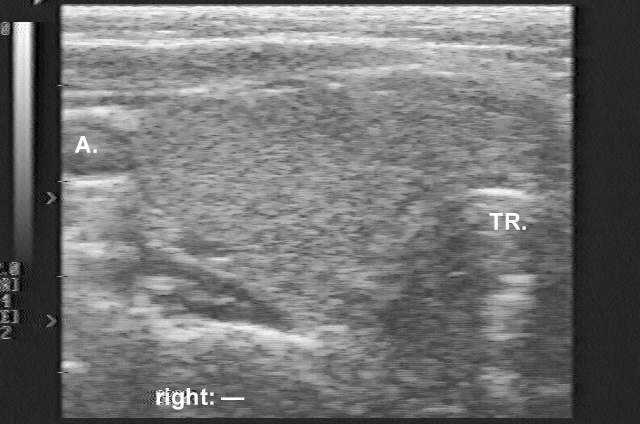

Clinical presentation: A 48-year-old woman who had been treated for Graves-Basedow's disease attended a follow-up examination. The patient had been examined 2 months earlier, when US was performed and revealed a nearly normal echo pattern without any discrete echo abnormality (see the first ultrasound picture). She was then well. Two weeks before the present examination, she felt dyspnea which progressed over the next 2 weeks.

Ultrasonography revealed a hypoechogenic inhomogeneous nodule in the right lobe of the thyroid (the second US picture). The palpable mass was a hypoechoic lesion which was located just ventral to the right thyroid lobe.